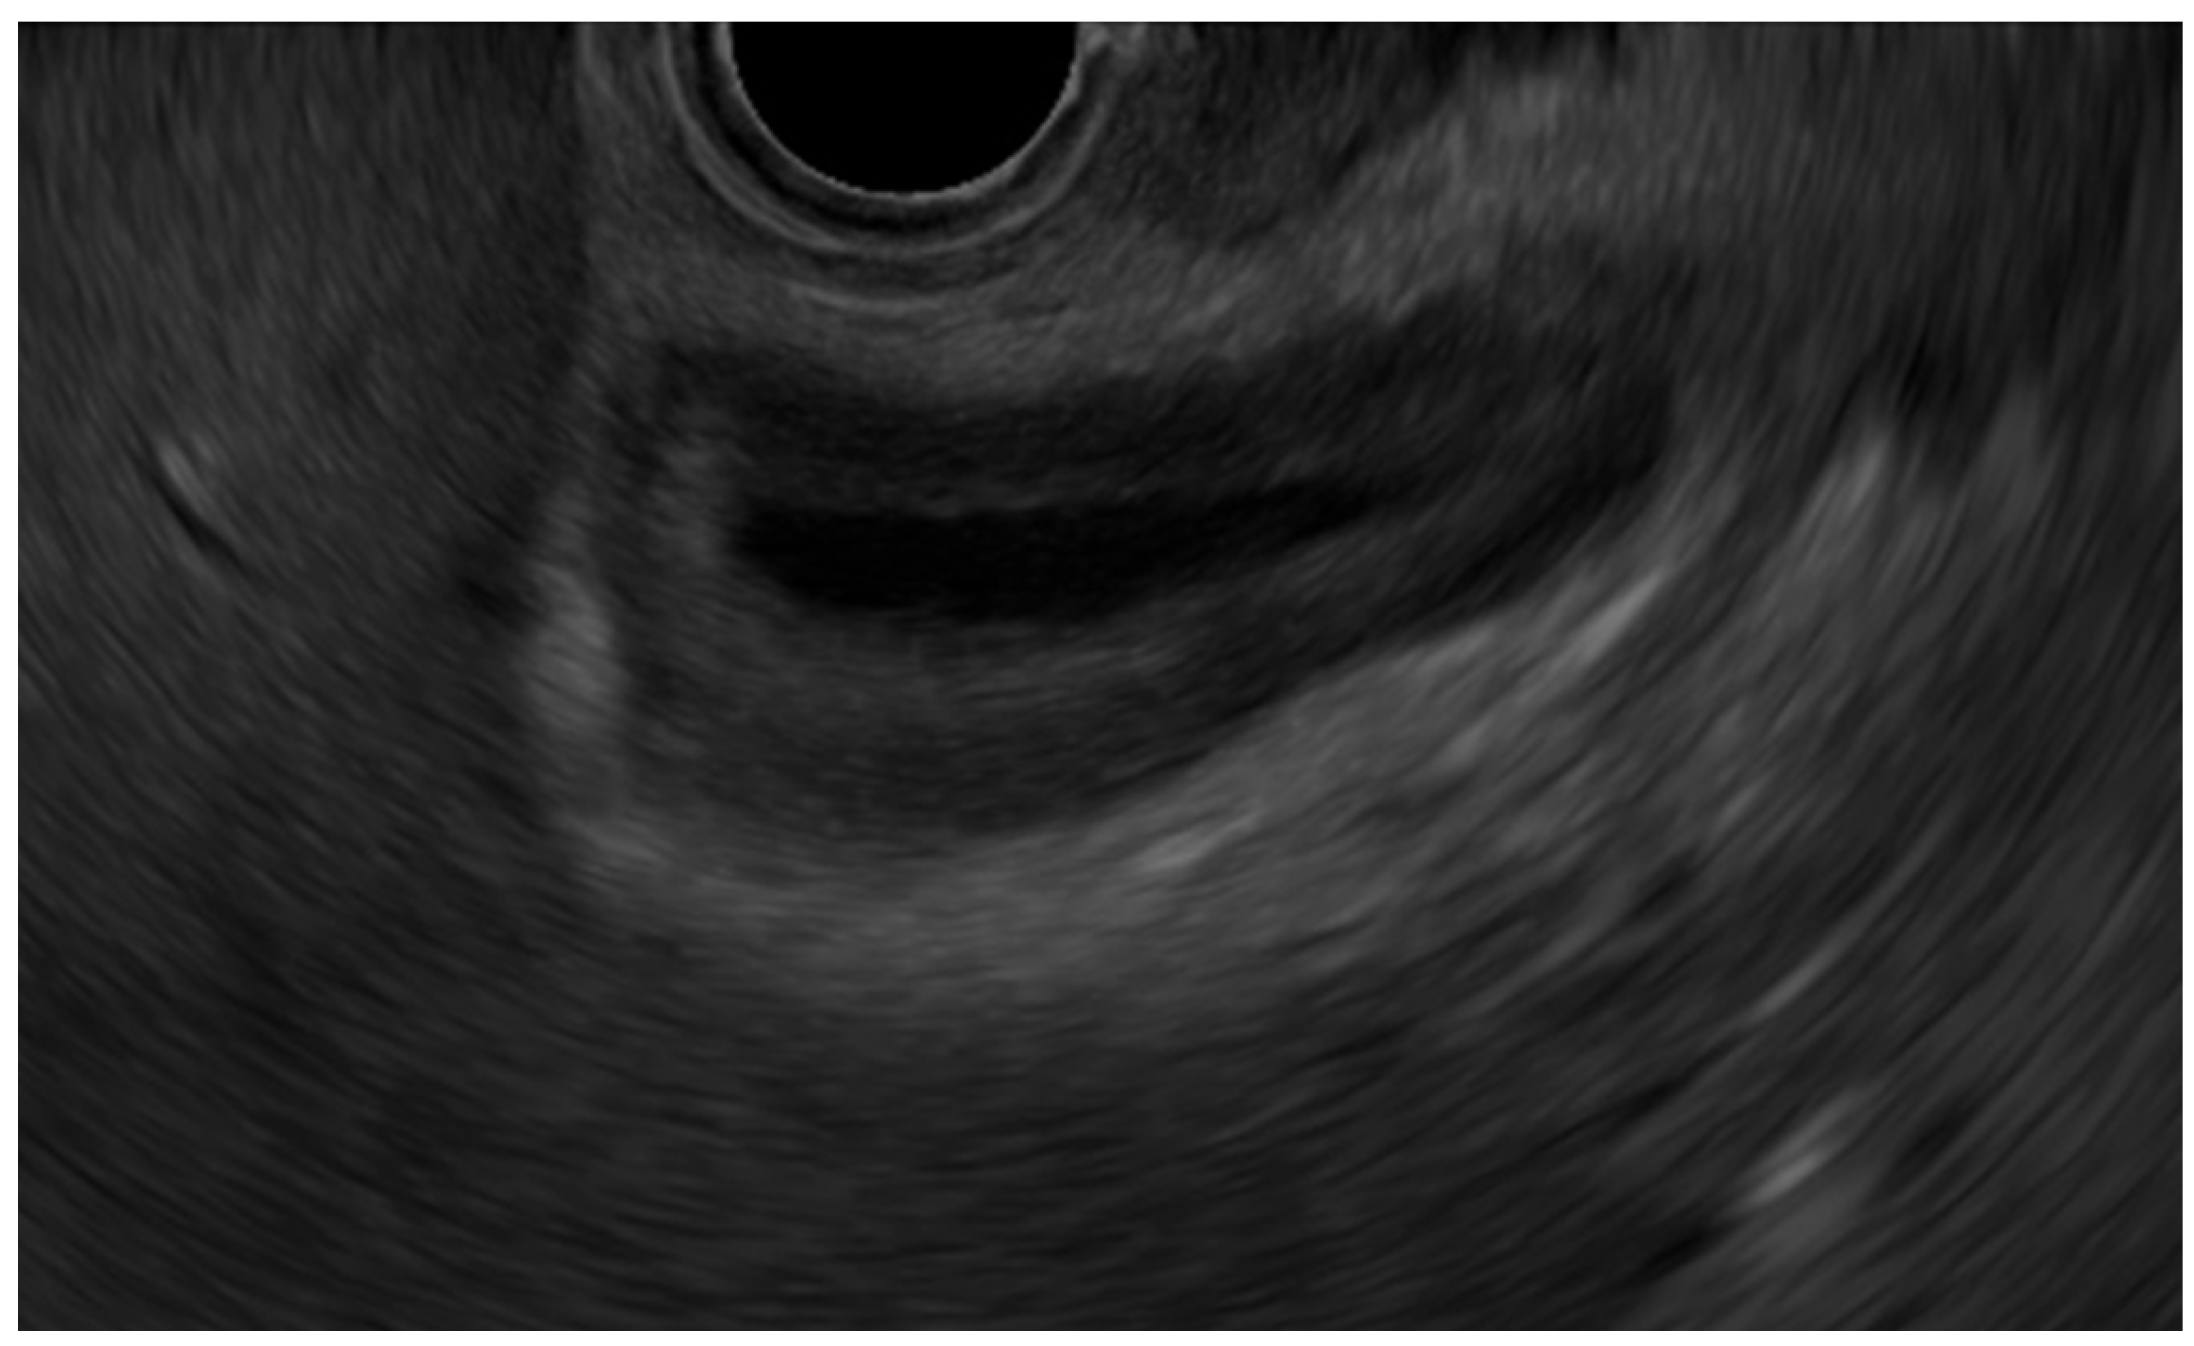

- Immunoglobulin G4-related sclerosing cholecystitis (IgG4-CC) (Figure 3)